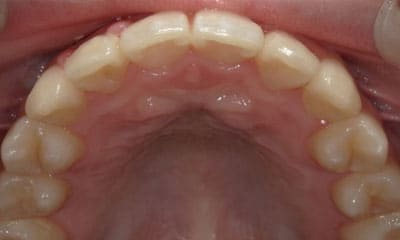

● 先天性の萌出方向異常を部分矯正で治療

藤沢デンタルオフィスの虫歯や破折で先天性の萌出方向異常を部分矯正で治療

01

02

03